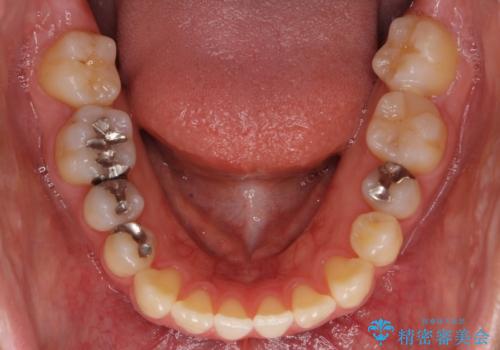

前歯のがたつき 若干受け口 インビザラインで

治療症例の内容

- 前歯のねじれおよび下の前歯が前に出ていることを気にして来院。

インビザラインで治療をおこないました。

前歯のねじれもなおり、比較的短期間でご満足いただけました。

部分矯正コースでしたので左下67の段差は特に治しておりません。

右下567及び左下6の虫歯治療も一緒に行っています。